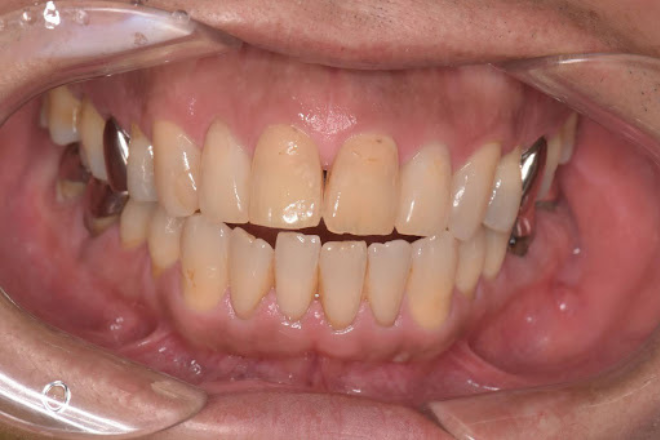

開咬とは、奥歯を噛んだときに上下の前歯の間に隙間ができてしまう状態のことです。

オープンバイトとも呼ばれ、不正咬合の一種に分類されます。

正常な噛み合わせでは、奥歯を噛んだときに上の前歯が下の前歯にわずかに重なります。

この状態であれば、前歯で食べ物を噛み切ることができます。

しかし、開咬の場合は、どれだけ奥歯を噛みしめても前歯同士が接触せず、隙間が残ってしまいます。